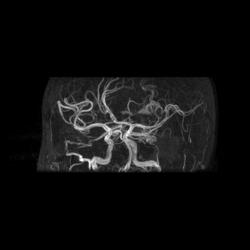

Артерио-венозная мальформация сосудов головного мозга.

3D TOF

При МР-ангиографии в режиме 3D TOF и 2D-TOF SPGR без применения контрастирующих веществ:

- определяется клубок расширенных и извитых патологических сосудов, получающих артериальную кровь из средней оболочечной артерии (ветвь наружной сонной артерии),  последняя расширена, из средней мозговой артерии и из задней мозговой артерии, эти артерии также шире, чем артерии контрлатеральной стороны. Дренирующие вены впадают в область стока синусов, а также в задний отдел верхнего сагиттального синуса

- дополнительно отмечены расширенные и извитые экстракраниальные сосуды, преимущественно под правой половиной задней черепной ямки.